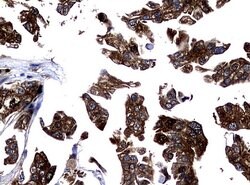

NME1 Mouse anti-Canine, Human, Rat, Clone: UMAB94, liquid, UltraMAB™

NME1 was identified because of its reduced mRNA transcript levels in highly metastatic cells. Nucleoside diphosphate kinase (NDK) exists as a hexamer composed of ′A′ (encoded by this gene) and ′B′ (encoded by NME2) isoforms. Mutations in the gene have been identified in aggressive neuroblastomas. Two transcript variants encoding different isoforms have been found for this gene. Co-transcription of this gene and the neighboring downstream gene (NME2) generates naturally-occurring transcripts (NME1-NME2), which encodes a fusion protein comprised of sequence sharing identity with each individual gene product.Specifications

| Immunocytochemistry, Immunofluorescence, Immunohistochemistry (Paraffin) | |